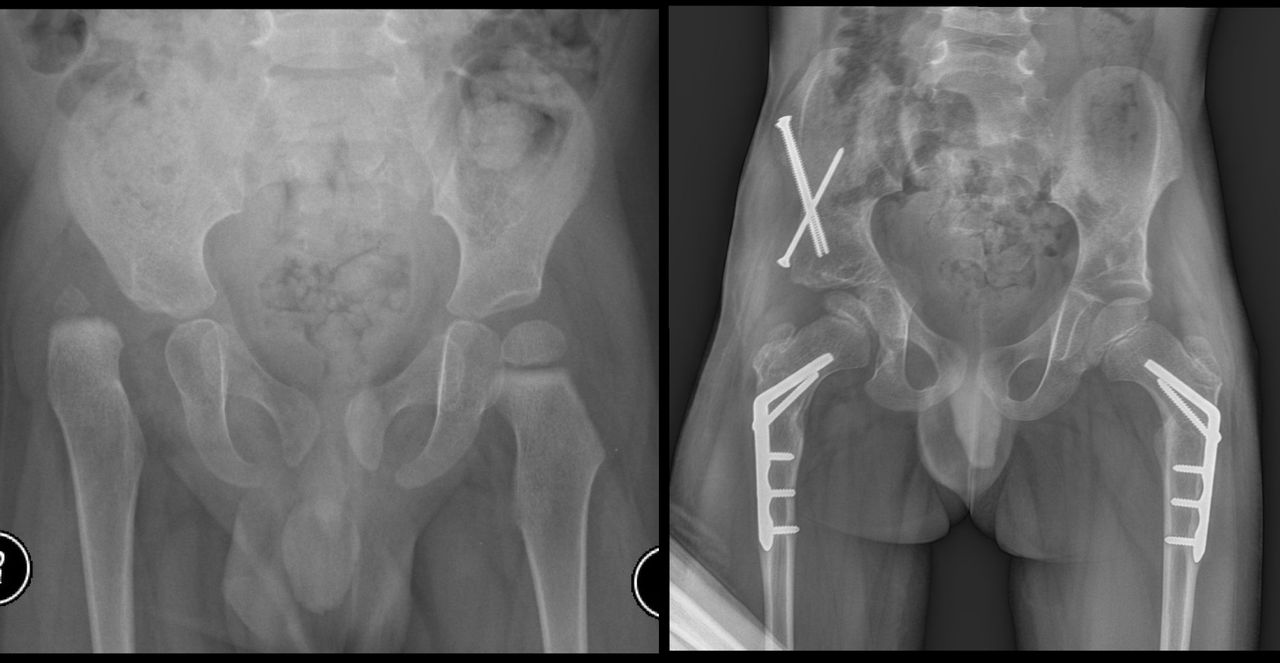

Jestem chirurgiem specjalizującym się w zaawansowanych rekonstrukcjach stawów oraz wydłużaniu kończyn dolnych (limb lengthening and reconstruction surgery). Kompleksowo opiekuję się osobami z problemami o podłożu ortopedycznym oraz neurologicznym, szczególnie dzieci z wadami wrodzonymi i schorzeniami nerwowo-mięśniowymi. Dzięki wieloletniemu doświadczeniu w nowoczesnych technikach rekonstrukcyjnych znacząco udoskonaliłem metody chirurgicznego leczenia dzieci z problemami neurologicznymi, otwierając przed nimi nowe możliwości poprawy funkcjonalności oraz jakości życia. Specjalizujemy się w jednoczasowych wielopoziomowych rekonstrukcjach kończyn (SEMLS) oraz kompleksowych rekonstrukcjach stawów biodrowych, łącząc sprawdzone techniki operacyjne z innowacyjnymi rozwiązaniami. Oprócz leczenia operacyjnego, koordynuje leczenie zachowawcze, obejmujące wielopoziomowe podania toksyny botulinowej (BTX) oraz minimalnie inwazyjne procedury, takie jak SPML (Selective Percutaneous Myofascial Lengthening) czy PERCS (Percutaneous Muscle Lengthening). Każdy pacjent otrzymuje indywidualnie opracowany program terapeutyczny, którego celem jest osiągnięcie najlepszych efektów przy minimalnym obciążeniu. Opiekuję się również pacjentami dorosłymi wymagającymi endopiotezoplastyki stawów oraz ratowaniem kończyn przed amputacją z powodu aktywnej lub przewlekłej infekcji W mojej pracy kluczowe jest podejście holistyczne, które łączy zaawansowane techniki chirurgiczne z terapią zachowawczą, aby zapewnić pacjentom kompleksową opiekę oraz trwałe efekty leczenia. Powierzenie nam zdrowia pacjentów jest dla nas ogromną odpowiedzialnością, a jednocześnie najwyższym zaszczytem. Zakres mojej specjalizacji obejmuje leczenie: 1. Wady wrodzone i rozwojowe kończyn: Hemimelia strzałkowa, niedorozwój kości udowej (CFD – Congenital Femoral Deficiency) – zaawansowane metody rekonstrukcyjne, w tym wydłużanie oraz procedury typu SUPERhip, SUPERankle Brak kości promieniowej i inne deformacje kończyny górnej – zabiegi ulnaryzacji, pollicyzacji, korekcji osi Mnogie wyrośla chrzęstno-kostne (MHE) – chirurgiczna korekcja deformacji i zapobieganie wtórnym ograniczeniom ruchomości Wrodzony staw rzekomy kości piszczelowej (CPT) – rekonstrukcja podudzia metodą CPT Xunion 2. Zaburzenia osi i długości kończyn: Skrócenia kończyn – techniki wydłużania z zastosowaniem gwoździ teleskopowych, aparatów Ilizarowa oraz STRYDE i PRECICE Zaburzenia osi kończyn (koślawość, szpotawość, rotacje) – korekcje wielopłaszczyznowe, osteotomie oraz stabilizacja z użyciem aparatów zewnętrznych i gwoździ wewnętrznych 3. Neuroortopedia – leczenie pacjentów z zaburzeniami neurologicznymi: Mózgowe porażenie dziecięce (MPD) – operacje zmniejszające spastyczność, korekcje stawów oraz zabiegi wielopoziomowe poprawiające funkcję chodu Przepuklina oponowo-rdzeniowa (spina bifida) – leczenie deformacji stóp i kończyn dolnych, stabilizacja stawów Artrogrypoza – wieloetapowe leczenie chirurgiczne poprawiające zakres ruchu i funkcjonalność kończyn 4. Zakażenia i zaburzenia zrostu kostnego: Osteomyelitis (zakażenia kości i szpiku) – leczenie chirurgiczne i antybiotykoterapia celowana Zaburzenia zrostu kostnego, brak zrostu (non-union, mal-union) – nowoczesne techniki transportu kostnego, przeszczepów i stabilizacji 5. Rekonstrukcja dużych stawów i leczenie deformacji: Endoprotezoplastyka biodra, kolana i stawu skokowego – zarówno w przypadkach zwyrodnieniowych, jak i pourazowych Choroba Legg-Calvé-Perthesa – metody operacyjne poprawiające ukrwienie głowy kości udowej i ograniczające deformację Złuszczenie głowy kości udowej (SCFE – Slipped Capital Femoral Epiphysis) – leczenie za pomocą zmodyfikowanej metody Dunna, pozwalającej na anatomiczną rekonstrukcję biodra i zachowanie funkcji stawu Dysplazje szkieletowe – interdyscyplinarne podejście do leczenia deformacji i ograniczeń funkcjonalnych 6. Leczenie stopy cukrzycowej i deformacji stóp: Stopa cukrzycowa – nowoczesne techniki rekonstrukcji stopy, zapobieganie amputacji Deformacje stopy (np. stopa końsko-szpotawa, płasko-koślawa, stopa sierpowata) – korekcja chirurgiczna i indywidualne podejście do biomechaniki chodu 7. Chirurgia urazowa dzieci i dorosłych: Leczenie złamań z zastosowaniem minimalnie inwazyjnych technik operacyjnych Rekonstrukcja kończyn po urazach, w tym ratowanie kończyny zagrożonej amputacją Stabilizacja wewnętrzna i zewnętrzna złamań patologicznych oraz pourazowych 8. Osseointegracja - zaopatrzenie pacjentów po amputacji poprzez korekcję kikuta lub aplikację osseointegracji do kości powyżej lub poniżej kolana wraz z zaopatrzeniem prtotetycznym 9. Wydłużanie kosmetyczne kończyn dolnych i górnych. Wykonujemy jednoczasowe operacje zarówno wydłużania kości udowych i piszczelowych jako jedyny ośrodek w Europie. Efekt jaki możemy uzyskać to 10-12 cm zwiększenia wzrostu. Wierzę, że najlepsze efekty leczenia można osiągnąć dzięki współpracy grona specjalistów, kierując się zasadą pacjentocentryzmu, która stawia potrzeby pacjenta w centrum procesu terapeutycznego.. Dlatego każda konsultacja odbywa się w interdyscyplinarnym zespole, w skład którego wchodzą ortopedzi, fizjoterapeuci, ortotycy i terapeuci zajęciowi. Pierwsza wizyta trwa około 1,5 godziny i obejmuje szczegółową ocenę stanu zdrowia oraz opracowanie planu leczenia chirurgicznego. W naszym instytucie działamy na podstawie indywidualnie opracowanych dla każdej jednostki chorobowej protokołów leczenia operacyjnego oraz postępowania fizjoterapeutycznego, których jestem współautorem. Dzięki temu zapewniamy spójne, kompleksowe i skuteczne podejście terapeutyczne, dostosowane do specyfiki danej choroby i indywidualnych potrzeb pacjenta. Zapraszam na konsultacje ortopedyczne, neuroortopedyczne oraz deformacyjne.